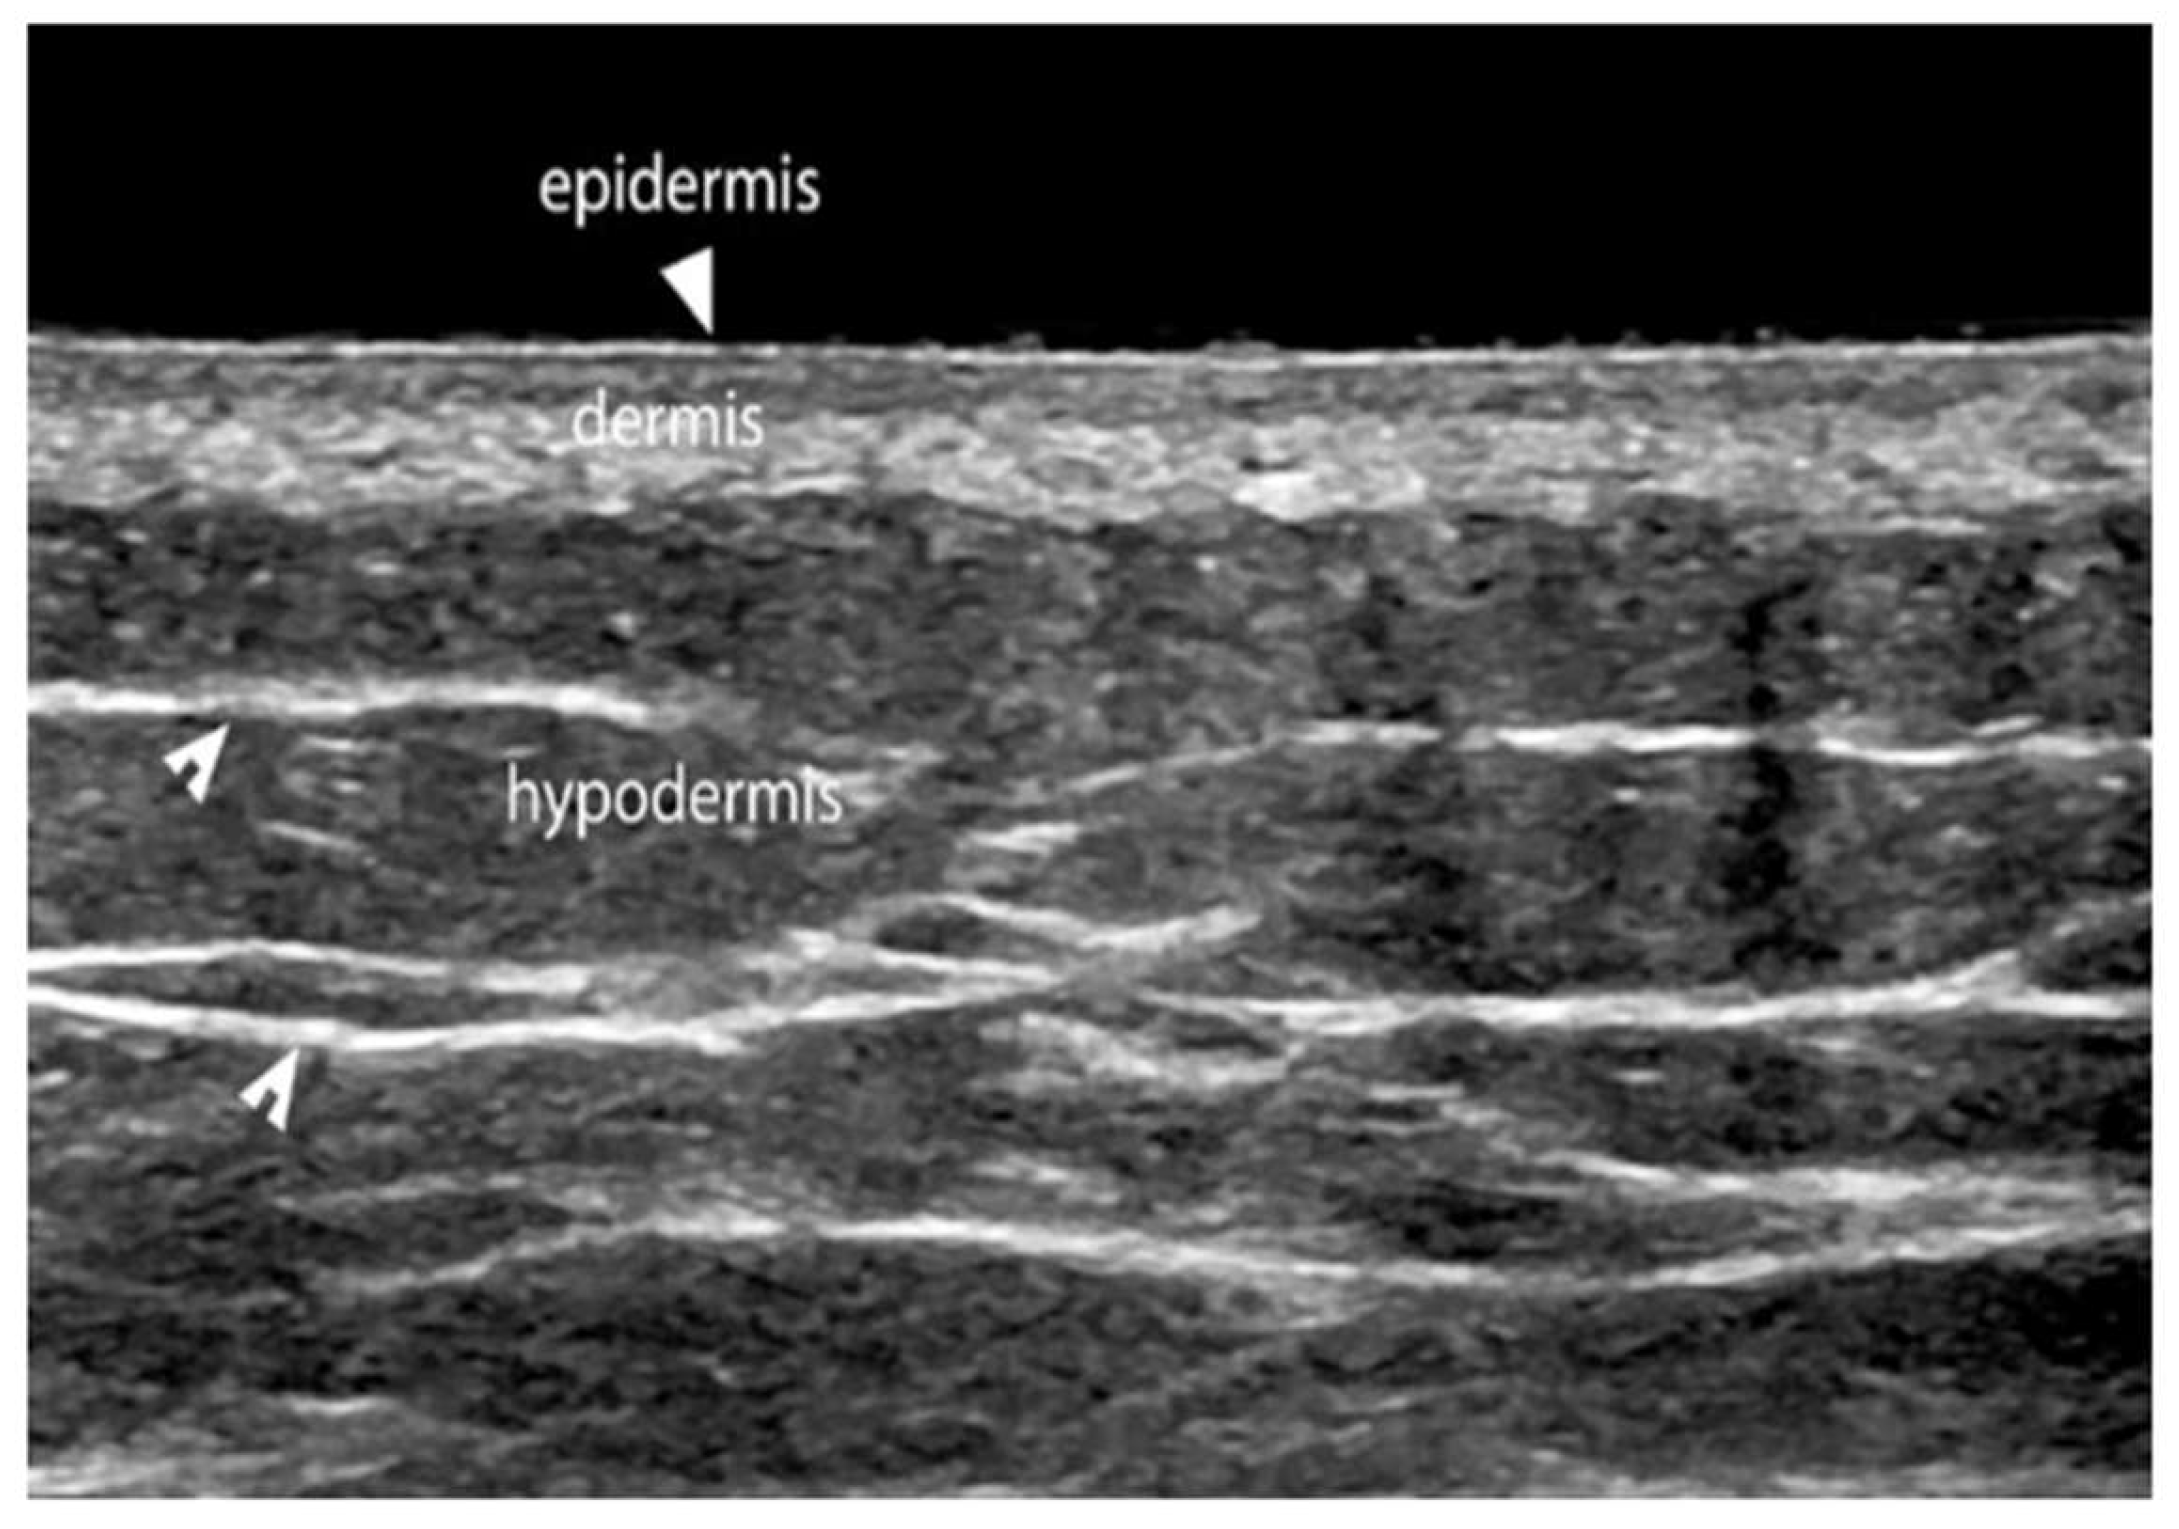

Ultrasound imaging of superficial tissues allows for the visualization of:

• Epidermis, the outermost layer, which appears as a thin, uniform hyperechoic line.

• Dermis, located deeper, which appears as a hyperechoic band (although less hyperechoic than the epidermis), with thickness varying according to the anatomical region. The dermis comprises a more superficial papillary dermis, which is more hypoechoic due to its high water content, and a deeper reticular dermis, which is more hyperechoic because of the density and orientation of collagen fibers. The epidermis, papillary dermis, and reticular dermis together form the dermo-epidermal complex (DEC).

• Hypodermis/subcutis (SUBC), the innermost layer, clearly separated from the DEC by the dermo-hypodermal junction, a continuous, well-defined line reflecting the structural differences between the dermis and hypodermis. The hypodermis appears hypoechoic, organized into lobules, and intersected by thin horizontal or oblique hyperechoic lines representing connective-tissue septa (scaffolds) through which lymphatic vessels run. These septa tend to be parallel to the muscular fascia and may form interconnections with it. The end of this layer is marked by the beginning of the muscular layer, and its thickness varies according to anatomical site and adipose-tissue content.

Figure 4. Ultrasound of superficial tissues in a healthy subject. The hyperechoic epidermis, the hypoechoic papillary dermis, and the hyperechoic reticular dermis can be identified, as well as the hypoechoic hypodermis traversed by hyperechoic fibrous septa.